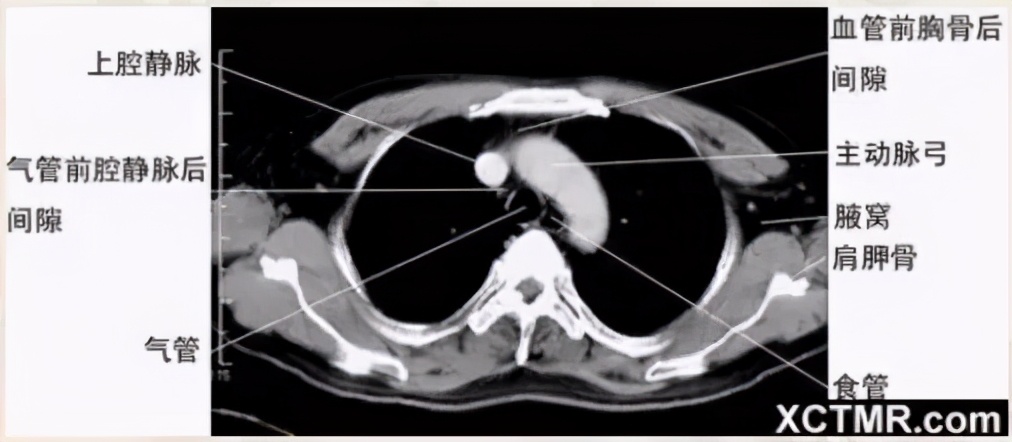

主动脉弓层面